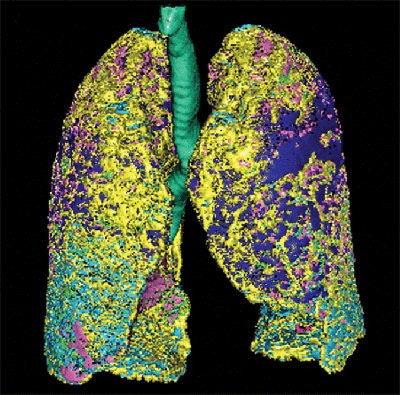

Images are of a 69-year-old man with idiopathic pulmonary fibrosis and emphysema. The patient was a former smoker (45 pack-years). Mean pulmonary artery pressure was 29 mm Hg, measured by right heart catheterization. Above left, computer-aided analysis showed 32.5% emphysema, 16% fibrosis, and 35.7% normal lung tissue volume. Above right and below, sagittal reformatted CT images show computer-aided segmentation results corresponding to the top left image. Pink = normal, dark blue = emphysema, light green = ground-glass opacity, light blue and yellow = fibrosis, dark green = trachea and bronchi, and orange = vessels. Images republished with permission from the American Roentgen Ray Society.

The lung volumes were examined on a computer-aided system that used CT attenuation values to distinguish fibrotic from normal, consolidated, and emphysematous regions on a PC. The automated tool extracts the lung from the CT images using a semiautomated threshold technique. Next, the bronchial trees and blood vessels are removed.

The algorithm categorized the lungs pixel by pixel, and then calculated the relative volume of each lesion to the CT lung volume as "normal(%)," "ground-glass opacities(%)," "consolidation(%)," "emphysema(%)," and "fibrosis(%)."